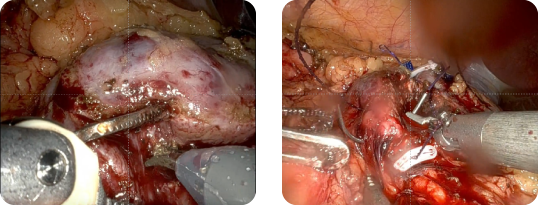

ECIRS

術中外観

Pass the ball

リソクラストによる砕石

右完全サンゴ状結石

ECIRS後